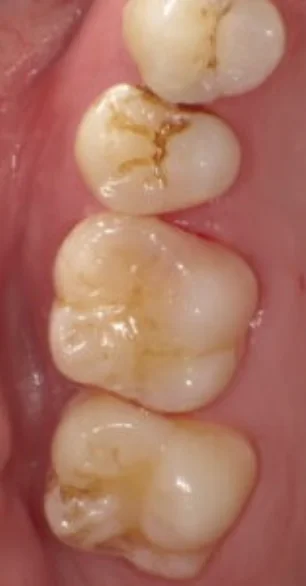

Before

After

むし歯をダイレクトボンディングで改善(30代女性)

1回 / 総額66,000円リスク・副作用:噛み合わせの変化で欠けたり、樹脂が水分を吸収して色が付いたりしてくるので定期的にケアを行いながら長く保たせる必要があります。